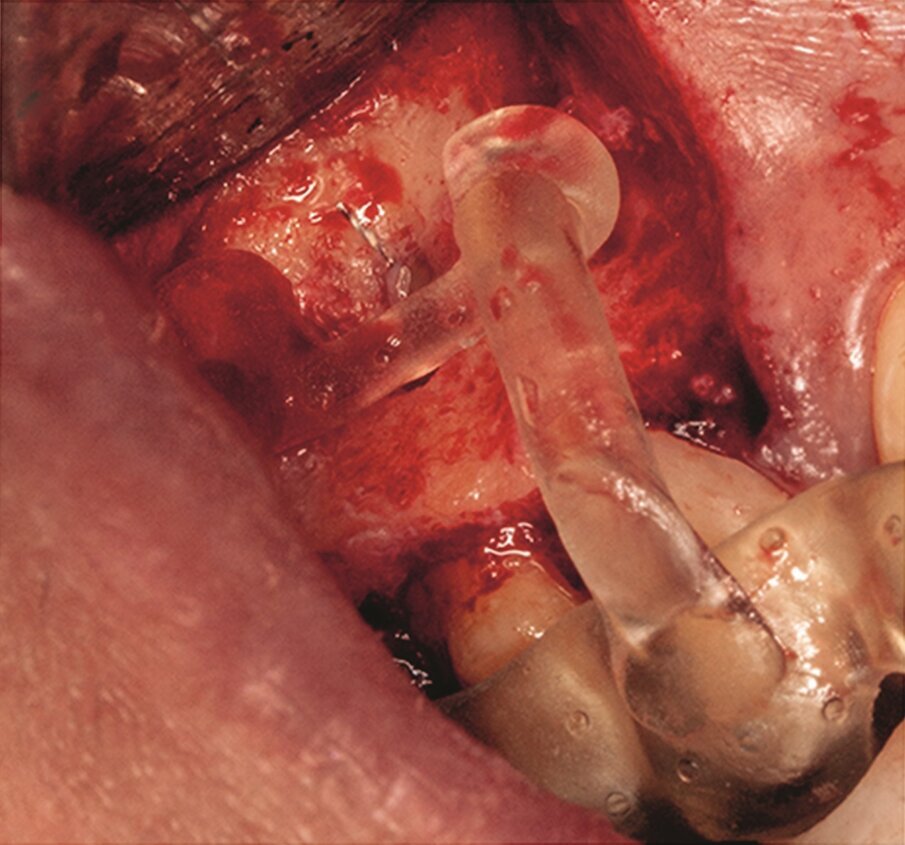

Fig. 1e–i: During microsurgery, the template was adjusted (e), …

… the limits of the cortical window were marked in the bone (f) …

… with a saw mounted in a Piezotome CUBE LED handpiece, then the bone was cut and removed (g & h) …

… to access the apical area and perform the apicectomy, apical cavity preparation and retro-filling of the mesial and distal roots (i).

Under local anaesthesia, a full thickness mucoperiosteal flap was reflected and the printed template was used to mark the cortical window, which was cut with a Piezotome CUBE LED handpiece (ACTEON), removed (Figs. 1e–h) and then placed in sterile saline. An apicectomy was done (Fig. 1i), and the mesial canals were retro-prepared with ultrasonic tips (NSK) and filled with EndoSequence BC RRM Fast Set Putty (Brasseler). The cortical window was then placed back and stabilized with collagen sponges in the gaps (collagen tape, Zimmer Biomet; Figs. 1j & k), and the ‑ap was sutured using 6/0 prolene suture material (Corpaul).